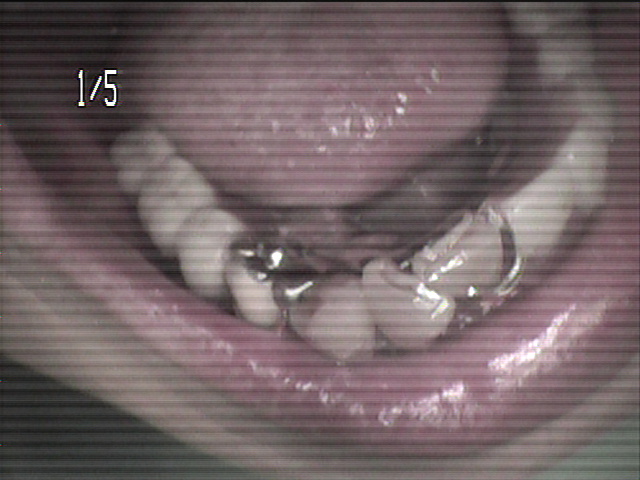

本日、出来上がりました自費の部分入れ歯ー下顎メタルプレートの症例です。

81歳の女性OUさんはとけも若々しいかたで、上下ともに、ぶぶん入れ歯ですが、今回は下顎の左右の奥歯のメタルプレートの入れ歯を新しく作りました。

自費によるメタルプレート義歯で、薄く丈夫な義歯として、とても舌感の良好な状態にすることができ、さらに自由な義歯の設計ができるため、残っているはにかける針金は白金加金で作成し、残存歯にやさしい設計となっており、舌に触れるバー部分はコバルトクロム合金で、丈夫に薄く作ってあります。

(参考代金;30万円)